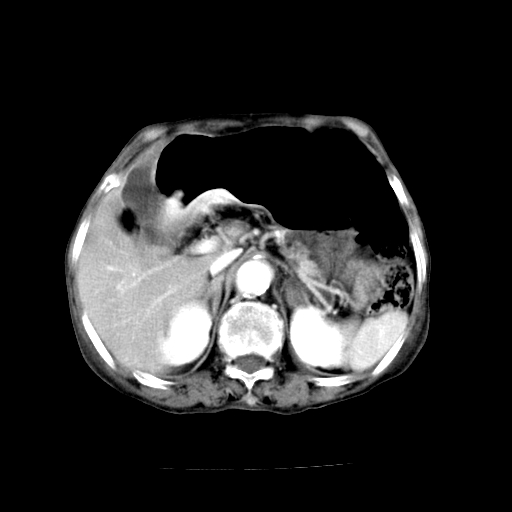

标题: CT19149:女,68岁,腹胀、恶心两周。 [打印本页]

女,68岁,腹胀、恶心两周,先做ct平扫,当时家属不同意强化,6天后家属要求增强扫描。

1、胃窦癌; 2、局灶性脂肪肝。

1、胃窦癌?建议行胃镜!; 2、局灶性脂肪肝。

1)胃窦壁厚,考虑胃窦癌?建议行胃镜检查。 2)局灶性脂肪肝。

支持考虑1、胃窦癌?建议行胃镜!; 2、局灶性脂肪肝。  3、双侧胸腔积液,胸膜增厚